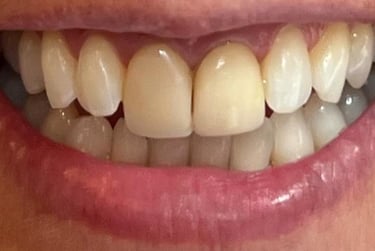

Cirurgia de aumento de coroa clínica antes das coroas

Caso que demonstra a vantagem da integração de diversas áreas da odontologia, unindo cirurgia, periodontia, prótese e estética para alcançar resultados funcionais e harmônicos.

Antes

Depois